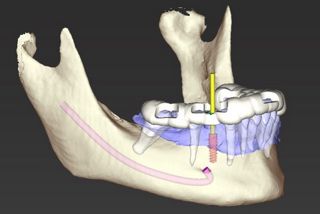

Abb. 3 - Digitales Design der chirurgischen Implantatführung (CoDiagnostiX) für die vollständig geführte statische computerunterstützte Implantatchirurgie [sCAIS].

Abb. 4 - Minimalinvasiver lappenloser Zugang mit 3D-gedruckter Bohrschablone und Metallhülse mit Tiefenmessgerät nach Pilotbohrung von okklusal.

Abb. 5 - Konsekutive vollständige Zahnextraktion nach dem geführten Implantatbohrprotokoll wie virtuell geplant mit Tiefenmessgerät in situ von lateral.